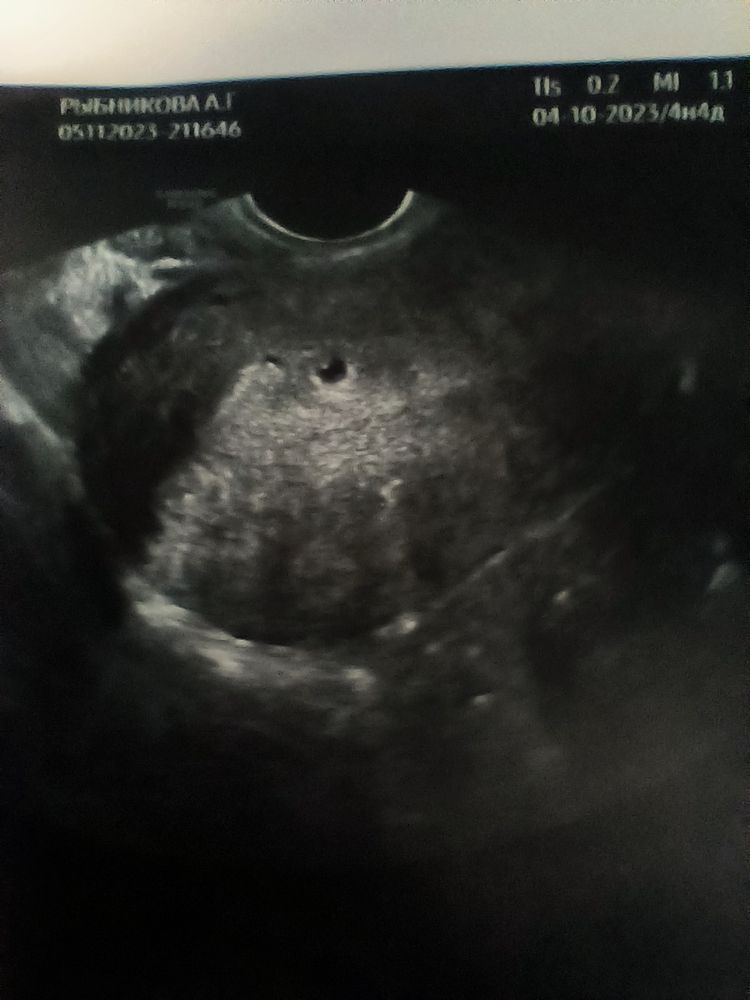

Вчера сходила на УЗИ, очень переживала по поводу внематочной и т.д. и т.п. Слава богу маточная, 4 недели 4 дня, плодное яйцо 4 мм, сказали придти через 10-15 дней чтобы услышать сердцебиение, надеюсь все будет хорошо 🌺 моя бусинка❤️❤️❤️